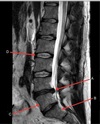

How well did you know this?

1

Not at all

2

Q

What is letter E?

A

CSF

3

4

5